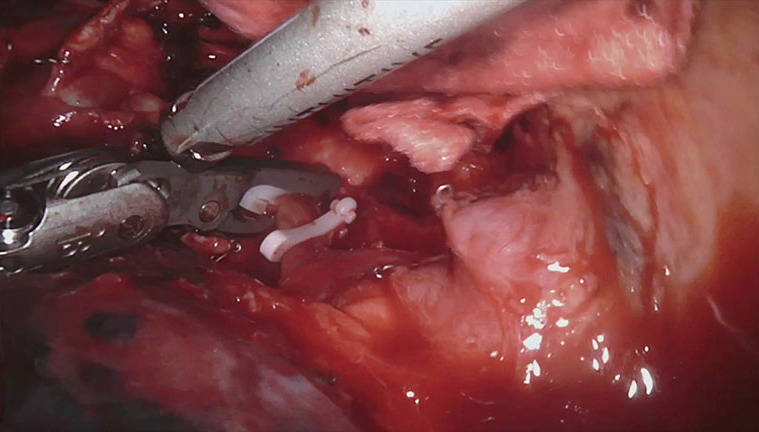

Figure 8.

Ascending branch of pulmonary artery is closed with two Hem-O-Lok® and then sectioned with harmonic device.

Figure 9.

Right upper lobe bronchus transected with stapler.